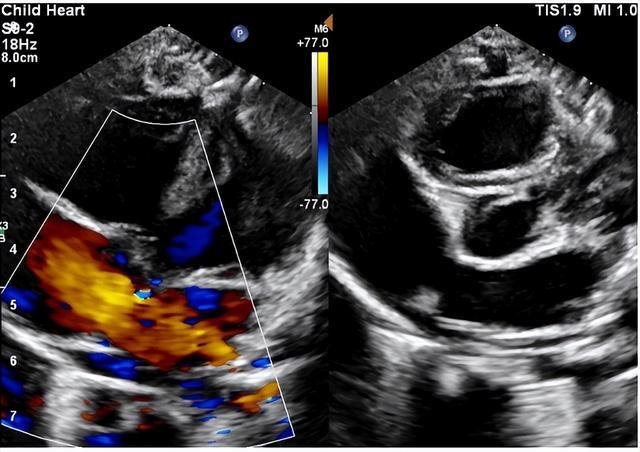

在赵源主任医师的耐心解释和坚持下,欣欣妈妈最终还是带宝宝来到超声医学科进行了心脏彩超检查,检查发现:先天性心脏病 房间隔缺损(继发孔型)。

目前绝大多数房缺根据临床表现及超声心动图即可确诊。心脏彩超检查是目前最简单直接的无创检查手段,可以发现房间隔缺损的类型、位置以及大小。并可以测量肺动脉压力评估有无肺动脉高压,评估右心的大小及功能。